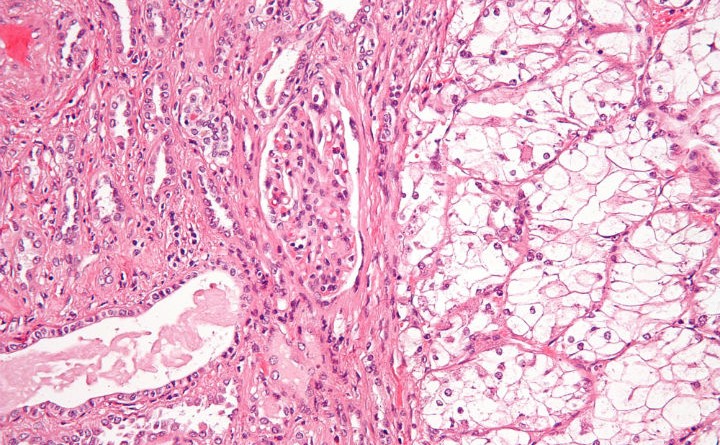

Renal cell carcinoma makes up approximately nine out of ten kidney cancer cases in adults. This type of kidney cancer originates in the lining of the proximal convoluted tubule, which is part of the small tubes in the kidney that transport waste from the blood to the urine. The symptoms of this disease are typically very hard to recognize, which explains why the cancer has often already spread by the time it is diagnosed.

Featured Image: Wikimedia